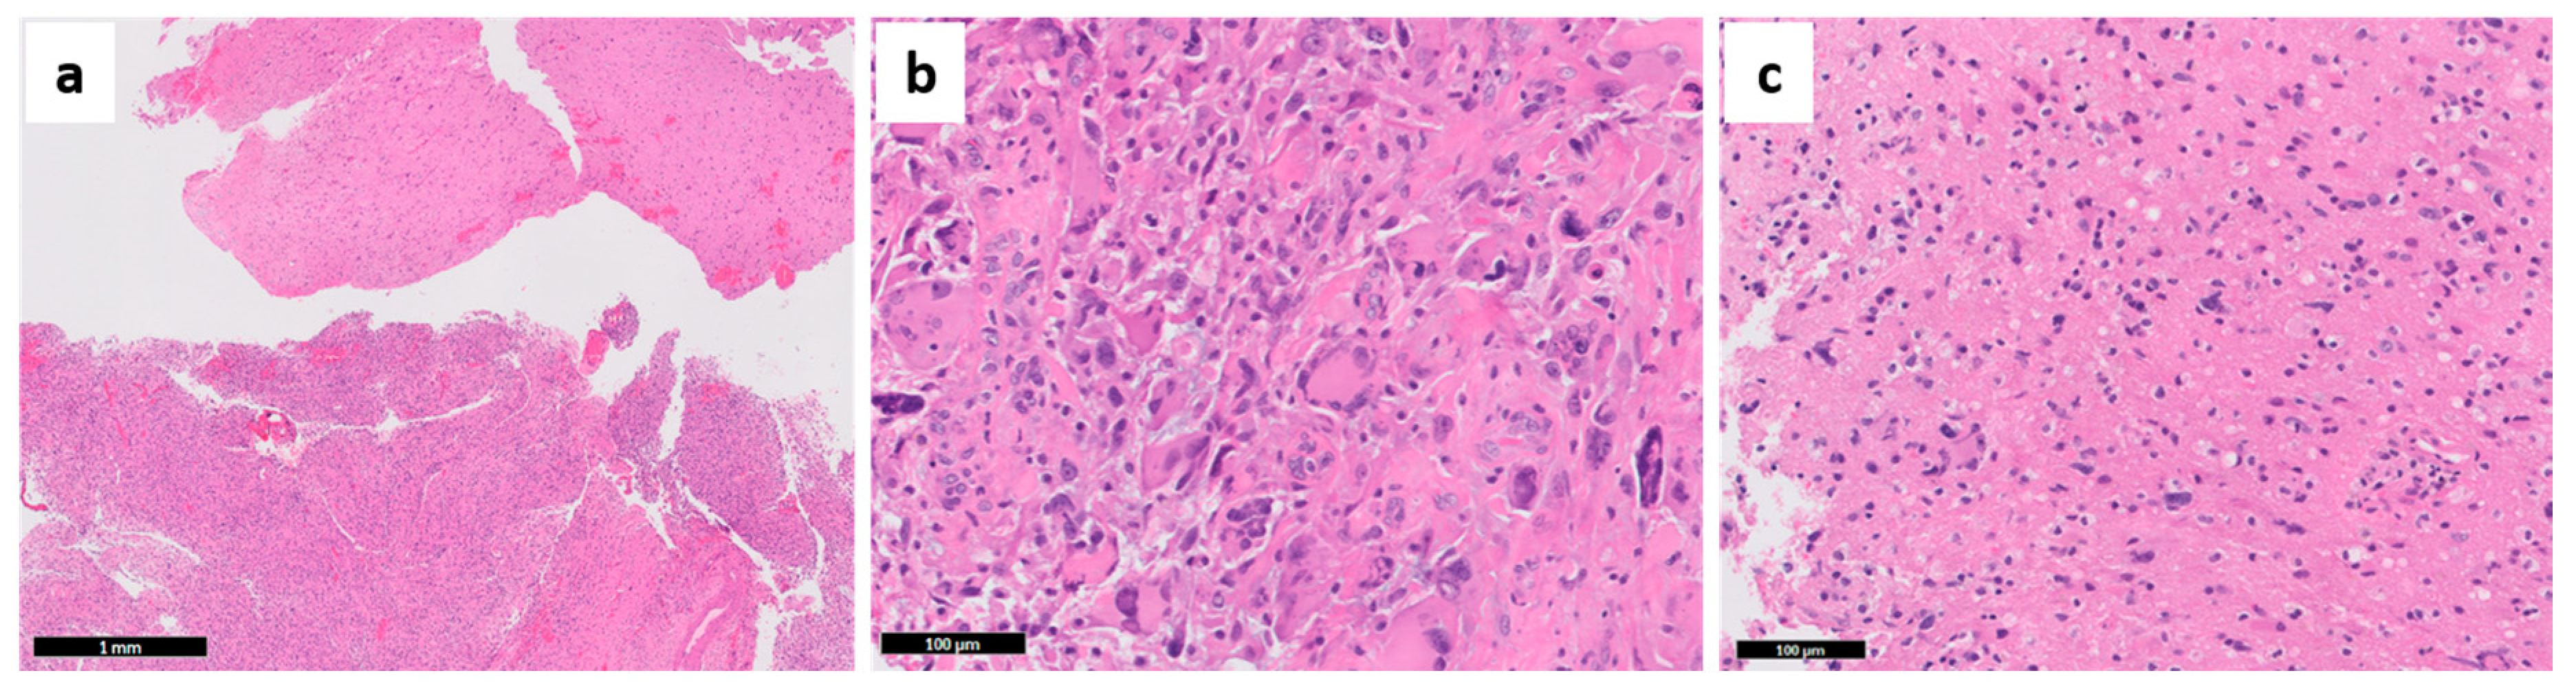

- Paulus, W.; Peiffer, J. Intratumoral histologic heterogeneity of gliomas. A quantitative study. Cancer 1989, 64, 442–447. [Google Scholar] [CrossRef]

- Giangaspero, F.; Burger, P.C. Correlations between cytologic composition and biologic behavior in the glioblastoma multiforme. A postmortem study of 50 cases. Cancer 1983, 52, 2320–2333. [Google Scholar] [CrossRef]